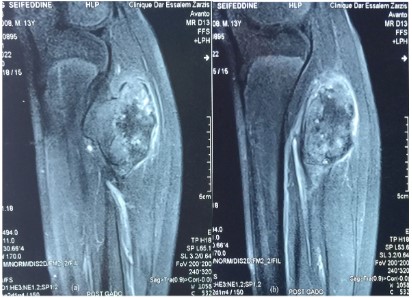

Magnetic resonance imaging confirms the benign aspect of the tumor with no invasion of the soft tissue , the CPN was in intimate contact with the tumor (Figure 4).

Figure 4: (a,b): Coronal T1weigted showing osteochondroma with large cartilage cap and contact with the CPN with no sign of sufferance.